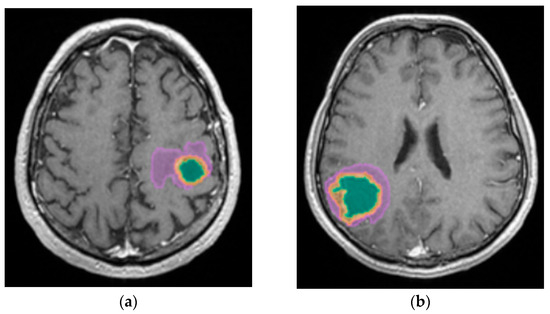

The automated segmentation was implemented using the mdbrain application, certified as a Conformité Européenne medical device of II class, developed by the German company of Mediaire, available in Romania through Supermedical. Mdbrain uses a DL algorithm consisting of a 3D convolutional neural network with a U-Net architecture [21]. The T2-weighted Fluid-Attenuated Inversion Recovery (T2W FLAIR) and T1-weighted contrast-enhanced (CE T1W) images were priorly combined in order to see the tumor and the edema on the same image, as the tumor enhances on the CE T1W images, and the edema shows a hyperintense signal on FLAIR and does not enhance [22]. The results of the Digital Imaging and Communication in Medicine (DICOM) imaging processing tool are seen in Figure 1.

Mdbrain processing of MRI brain acquisition (DICOM) (Scale 1:20). T1W CE in sagittal, coronal and axial planes, respectively. View of the three regions that were calculated separately for every patient: green—necrosis, orange—enhancing part of the tumor and purple—perilesional edema (approval was obtained from the Ethics Committee of the University of Medicine and Pharmacy “Grigore T. Popa” Iasi).